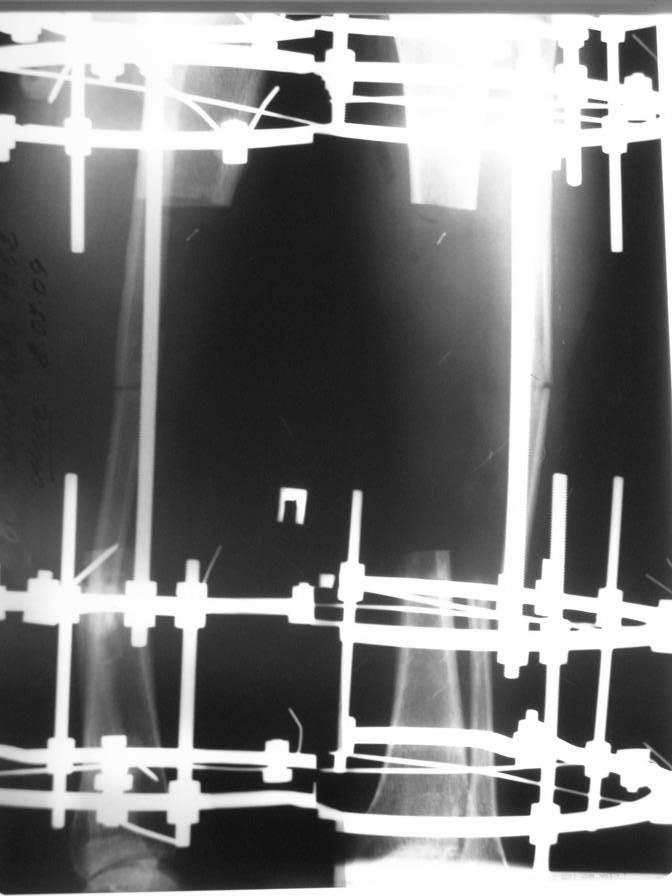

Доброго времени суток. Около двух месяцев назад я писал о пациенте с открытым двойным переломом костей голени, которому в районной больнице производилась открытая репозиция перелома большеберцовой кости с фиксацией металлической пластиной. После нагноения раны металлическая пластина удалена, в рану на большом протяжении обнажилась большеберцовая кость, больной в последующем около 2-х месяцев вёлся на скелетном вытяжении, предпринимались попытки стянуть рану на передней поверхности голени местными тканями путём нанесения параллельных ране разрезов по боковой поверхности голени. К нам он поступил спустя три месяца после травмы с гнойной раной на передней поверхности голени, в которой была обнажена на большом протяжении тусклая большеберцовая кость.На операции в костно-мозговом канале большеберцовой кости гной, кость тусклая. Была произведена резекция участка большеберцовой кости длиной 17 см, пластика дефекта мягких тканей переденей поверхности голени передней большеберцовой мышцей, которой так же укрыт верхний и нижний отрезки большеберцовой кости, мышца закрыта расщеплёнными кожными лоскутами, кости голени фиксированы в аппарате Иллизарова. Послеоперационный период протекал без осложнений, все лоскуты прижились, мелкие раны зажили рубцеванием, воспаления мягких тканей вокруг спиц нет. Недавно оперирован повторно- малоберцовая кость пересечена на уровне верхнего и нижнего отрезков большеберцовой кости, перемещена на область дефекта большеберцовой кости, фиксирована в аппарате. Рентгенснимки и фото голени больного прилагаю. Послеоперационный период протекал без осложнений, раны зажили, швы сняты, больной ходит с полной опорой на ногу в аппарате, воспаления мягких тканей вокруг спиц нет. Планируется постепенное увеличение нагрузки на перемещённую малоберцовую кость путём этапного удаления спиц под рентген контролем. С уважением, Цветков Евгений.

ВОЗМОЖНО В ТАКИХ СЛУЧАЯХ БИОС С ПОСЛЕДУЮЩИМ ТРАНСПОРТОМ РЕГЕНЕРАТА. КОМПОНОВКУ АППВРАТА МОЖНО ИСПОЛЬЗОВАТЬ ТАКУЮ (ФОТО ИЗ КЛИНИКИ ПРОФ. ФРИДРИХА - БРЕМЕН)